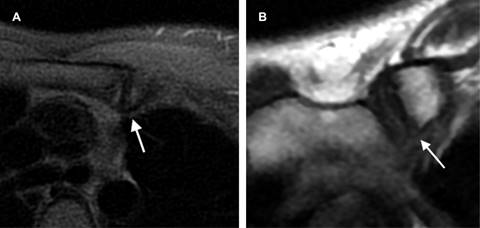

Mujer de 22 años que inicia con dolor focal y aumento de volumen en topografía de la articulación esternoclavicular izquierda de tres semanas de evolución. Negó traumatismos o algún otro factor desencadenante. Su médico le solicitó resonancia magnética, en la cual se aprecia engrosamiento e irregularidad del cartílago articular con predominio en la región inferior-interna de la articulación, asociada a edema subcondral (Figura 1).

Figura 1: Resonancia magnética de la articulación esternoclavicular izquierda; A) plano axial, donde se observa aumento en la intensidad de señal en secuencia STIR correspondiente a edema subcondral; B) plano coronal en secuencia T2 con engrosamiento del cartílago de manera generalizada.